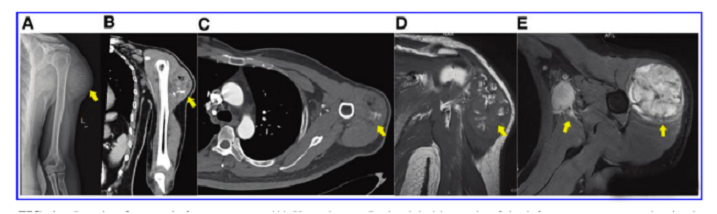

接受iPS細胞治療患者的畸胎瘤。(A) 在左上臂的三角肌中,觀察到一個圓形的混合密度腫塊,邊界不清,為9.6±5.2cm。(B) CT冠狀掃描顯示三角肌內(nèi)有一圓形混合密度腫塊,邊界不清。(C)增強CT軸向掃描顯示不均勻和中度強化。(D)MRI T1W以等信號為主,有不規(guī)則的高低信號區(qū)。(E) T2W也顯示高信號和斑片狀低信號區(qū),左腋窩有多個淋巴結(jié)腫大。

文中展示了該未成熟畸胎瘤的臨床,放射學和病理學特征,作者認為這種腫瘤不同于典型的未成熟畸胎瘤,特點是快速增長和局部淋巴結(jié)轉(zhuǎn)移,該新生腫瘤對典型化療方案沒有反應,磁共振成像顯示腫瘤的不均勻強化和豐富的血供。